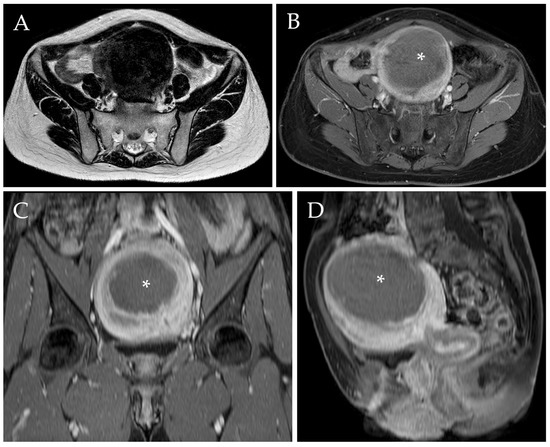

Radiological evaluation of the myomas was assessed through TV-US or MRI independently by two radiologists with 3 and 10 years of experience in the field, both before the procedure (Figure 2) and after 1 year. MRI scans were performed using the same 1.5T MRI superconductive scanner (HDX-t Signa; General Electric®, Milwaukee, WI, USA). Pelvic MR scans included pre-contrast axial T1-w images, pre-contrast axial, sagittal, and coronal fat-saturated T1-w images, axial and sagittal T2-w images, axial diffusion-weighted images (DWI), and axial, sagittal, and coronal fat-saturated T1-w images after intravenous administration of gadolinium-based contrast agent (0.1–0.2 mmol/kg; Gadovist ®, Bayer-Schering Pharma, Berlin, Germany) [7,53].

Figure 2.

MRI of a 46-year-old woman complaining of metrorrhagia and pelvic pressure. Axial T2-w image (A) demonstrated the presence of a voluminous myoma localized in the fundal region, measuring approximately 140 mm. Axial, sagittal, and coronal post-contrast T1-w images with fat saturation demonstrated the typical enhancement of the mass (B–D).